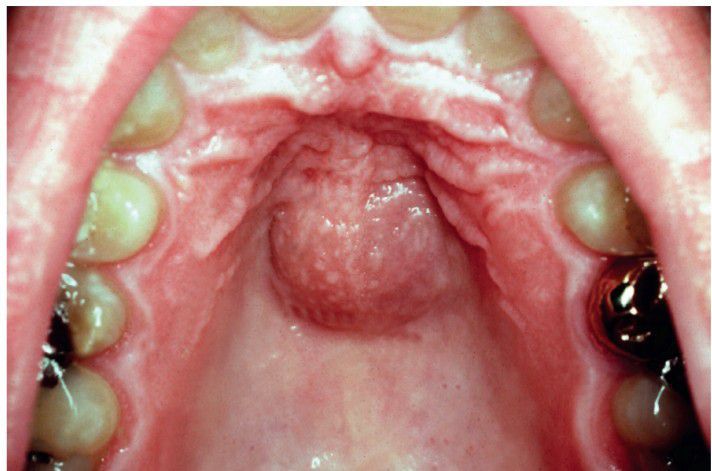

Median palatal cyst

Median Palatal Cyst. Compressible mass in the midline of the hard palate posterior to the incisive papilla. (Courtesy of Dr. Craig Fowler.)